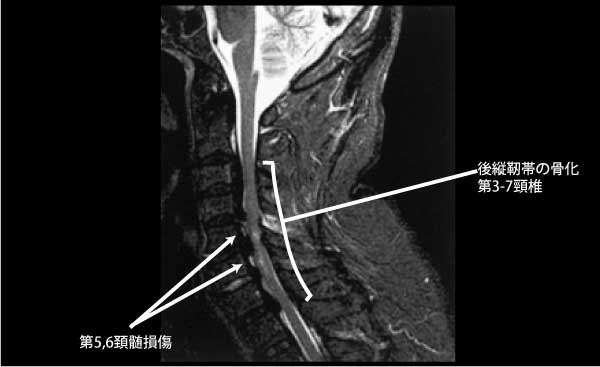

強い外力(交通事故・転落・スポーツ)で脊髄実質が挫傷し、浮腫・出血・圧迫により損傷高位以下に運動・感覚麻痺が出現。完全麻痺と不全麻痺に大別。